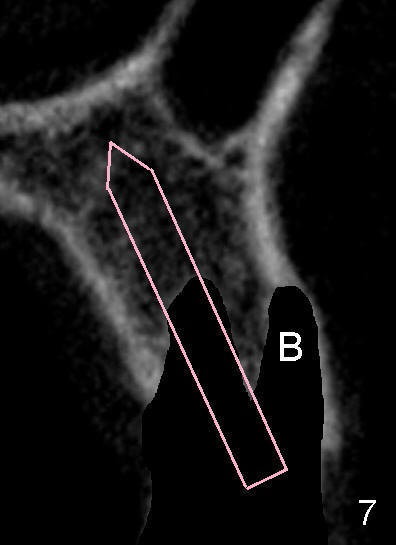

After tooth extraction, the osteotomy is initiated in the palatal socket (compare Fig.6,7 (CBCT, not the same case) with a pilot drill (pink outline). The osteotomy is enlarged by a series of reamers until the apical diameter (3.5 mm, Fig.8) of the prospective tapered implant (5x20 mm, Fig.9 I). The socket is obliterated by the tapered implant (Fig.9) with simultaneously achieving primary stability. This looks less over engineering than the first case.